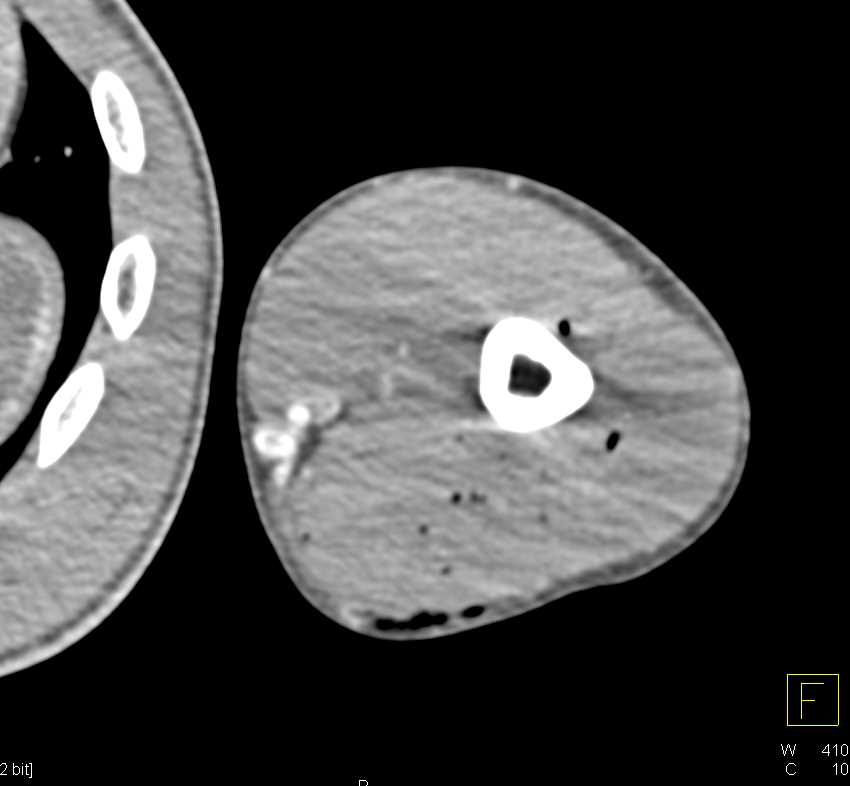

GSW With Decreased Vascular Flow and Small Distal Arterial Map